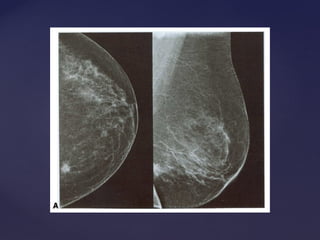

Padrão mamográficoPadrão mamográfico

Descrição Acurácia Diagnóstica

Lipossubstituídas (até 25% de tecido

glandular)

Muito alta

Parcialmente lipossubstituídas (26 a 50% de

tecido glandular)

Alta

Densas e heterogêneas

(51 a 75% de tecido glandular)

Limitada

Muito densas (>75% de tecido glandular) Limitada